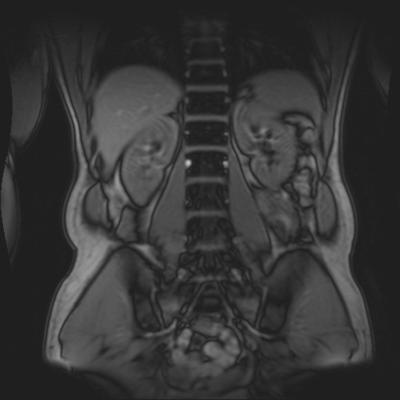

I had an MRI 12 days after the initial onset. This showed a slight disc bulge and small fissure in the disc (L4).

I wouldn't go back to the gym, well that's my opinion. You've obviously had a slipped disc (incidentally, it looks like the L5-S1 disc from the scan but I don't have all the views), and it takes a good deal more than a month to heal once the bulge has been reduced. The chances of a second slip are great at this stage. Be careful.